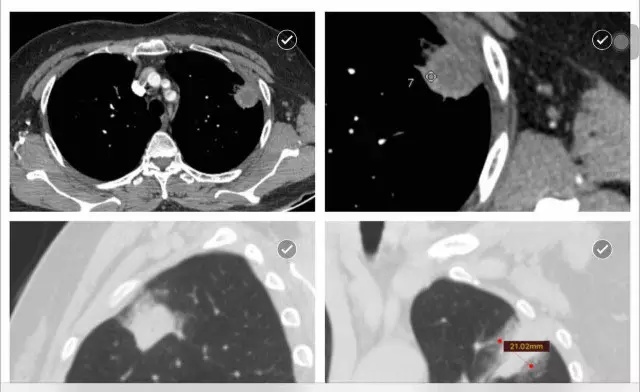

患者咳血胸痛一周。

肺部占位。

病变考虑为肿瘤或炎症,血象不高,肿瘤序列正常,结核试验阴性,ect阴性。请问贺主任意见?

左肺上叶尖段可见4.5*1.8cm的楔形实变病灶,尖端朝向肺门,周边可见浸润样实变。病灶中央可见低密度的无强化区,可见引流支气管;相邻胸膜可见增厚。会诊意见: 左肺上叶实变病灶,中央有液化坏死,考虑炎症性病变,霉菌、隐球菌或结核,请结合临床和治疗变化。供参考。建议最后提供原始轴位图像。

和缓医生结核实验阴性,白细胞8000多,有咳血。

病灶形态比较单一,不支持结核。但糖尿病患者结核可以有此表现。可以按照炎症治疗动态观察,三周。

没有糖尿病病史。谢谢贺教授,我们也诊断炎症,建议抗炎治疗两周后复查,胸外科考虑肿瘤,建议手术。

最好治疗观察。